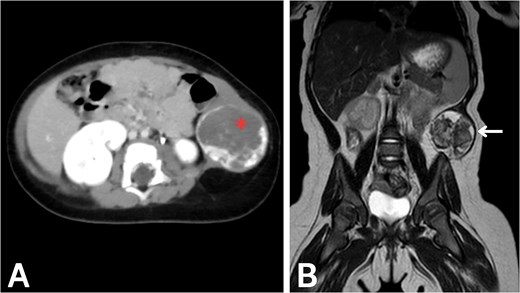

To evaluate potential intra-abdominal involvement and further characterize the mass, a contrast-enhanced computed tomography (CT) scan was performed first. As shown in Fig. 1A, the CT scan revealed a 4.3 × 4 × 4 cm round, heterogeneous mass in the left lateral abdominal wall, containing internal calcifications. The mass showed significant peripheral enhancement during the arterial phase, with centripetal filling observed in the delayed phase. Several feeding vessels were noted, the most prominent being the left inferior epigastric artery. Additional vessels were noted to arise from the internal and external iliac arteries, as well as a descending vessel from the left lateral inferior chest wall. These imaging findings were highly suggestive of a vascular malformation, although the possibility of a hemangioma could not be entirely excluded. The differential diagnosis at this stage included rhabdomyosarcoma, fibromatosis, hemangioma, and lymphatic malformation.

Imaging of the abdominal wall mass. (A) Axial post-contrast CT image in the venous phase demonstrates peripheral centripetal enhancement of the lesion (asterisk). (B) Coronal T2-weighted MRI reveals the anatomical relationships of the mass (arrow).

After CT confirmed the mass’s location in the abdominal wall, magnetic resonance imaging (MRI) was performed to delineate the mass and soft tissue involvement further. As shown in Fig. 1B, the MRI confirmed the presence of a heterointense mass in the left lateral abdominal wall, with peripheral enhancement consistent with a vascular malformation. The liver, spleen, and both kidneys appeared normal on imaging. Given the highly vascularized nature of the lesion on imaging, percutaneous biopsy was deemed high-risk; therefore, surgical excision was recommended for both diagnostic and therapeutic purposes.